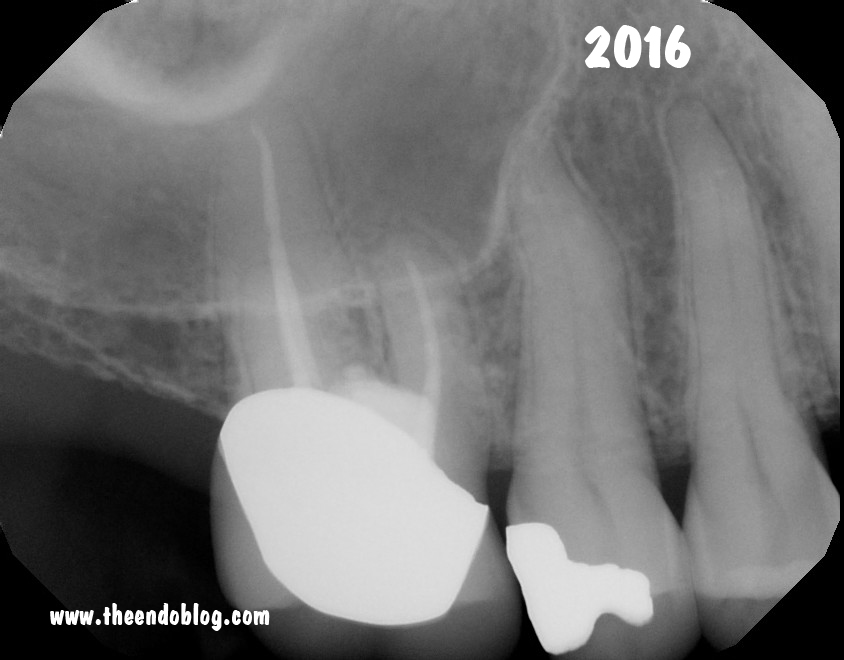

Fortunately,

with good repair materials, the prognosis for a tooth like this is

still good. A 7 year recall finds the tooth in full function and

asymptomatic.